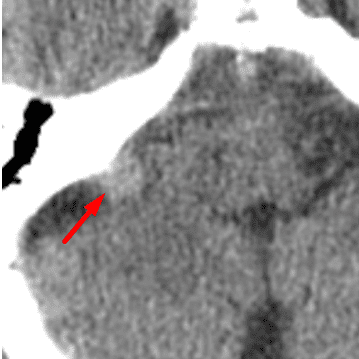

Optic Disc Drusen

Case 14

Free